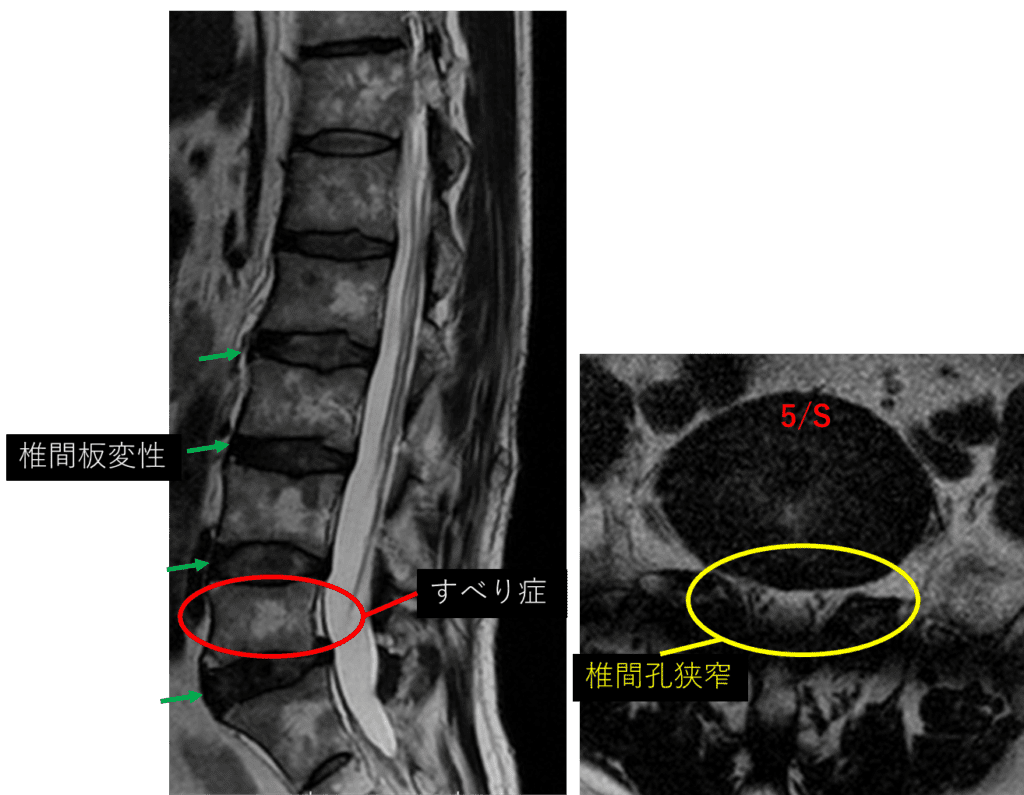

L1/2: 異常なし

L2/3: 異常なし

L3/4: 軽度椎間板変性

L4/5: 椎間板膨隆

L5/S: 椎間板変性、椎間板膨隆、すべり症

以上の事が画像上認められます。

椎間板変性、すべり症 を認め、主症状の原因の可能性が高い。